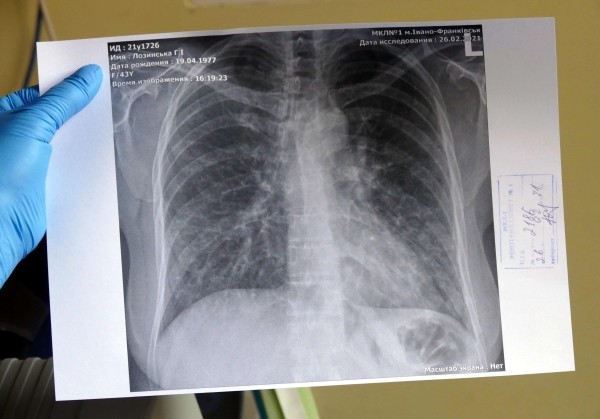

Фото: РИА Новости/ Игорь Маслов